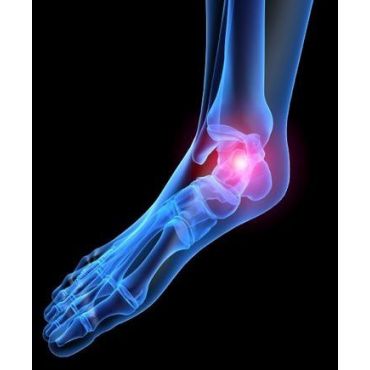

Your feet are the foundation of your body.

When you are experiencing problems with or pain in your feet, it affects your well being. These problems can make it difficult to manage all aspects of your life in a healthy and productive way. Seeing a podiatrist could be the right answer.

Our podiatrists are here to help you build a strong and healthy foundation by addressing any podiatric issues that may be keeping you from your best self.